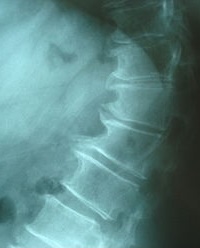

- تعد فحوصات التصوير بالرنين المغناطيسي والتصوير المقطعي المحوسب مفيدة في تشخيص الألم ولكنها ليست نهائية بشكل عام ويجب أخذها في الاعتبار مع الفحوصات الجسدية والتاريخ.[5]

التشخيص

هناك العديد من التقنيات المستخدمة في تشخيص داء الفقار ، وهي ؛